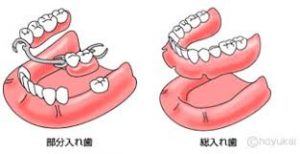

※入れ歯とは

奥歯がなくなって、ブリッジができない場合や歯が全部なくなってしまった場合に、上図のように残っている歯にバネをかけて歯を作る方法です。総入れ歯の場合は歯茎で支えることになります。